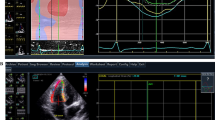

In healthy subjects, the RV generates pressure mainly by longitudinal shortening5. In contrast, in subjects with structural abnormalities in the RV, etiology-specific shortening patterns (e.g., degenerated RV vs. overloaded RV) have been reported rarely. Currently, the evaluation of strain assessment on CMR using feature tracking is increasing in clinical practice6. RV longitudinal strain has prognostic importance in various cardiac diseases7. Furthermore, while the clinical application of RV circumferential strain appears to be limited compared with that of longitudinal strain, the usefulness of evaluating RV circumferential strain has been reported in patients with pectus excavatum8 and in some SLE cases7. Through-plane motion may affects 2D measures of circumferential strain using a fixed imaging plane (Fig. 1). It is also known in echocardiography that through plane motion affects LV circumferential strain in 2D measurements9. Strain analysis using 3D echo of the right ventricle has been utilized in recent years and has been reported to be effective as a prognostic factor10, but analysis also requires additional software and equipment and is not highly available at this time.

RV migration in the fixed LV short axis slice. Cine CMR of a subject with no structural abnormalities in the RV. In the four-chamber views, the RV portion marked by the blue arrows migrates in the cardiac cycle (a, b). (c) The LV short axis view along the red reference line in diastole. (d) The LV short axis view along the red reference line in systole. Circumferential strain was assessed between (c, d) on the same red reference line, regardless of the RV longitudinal shortening. (e) The LV short axis view along the green reference line in systole. Between (c) and (e), more significant circumferential shortening (than that seen in (d)) and the same structure of the RV (yellow visual cues) are visible. RV Right ventricle, LV Left ventricle, CMR Cardiac magnetic resonance.